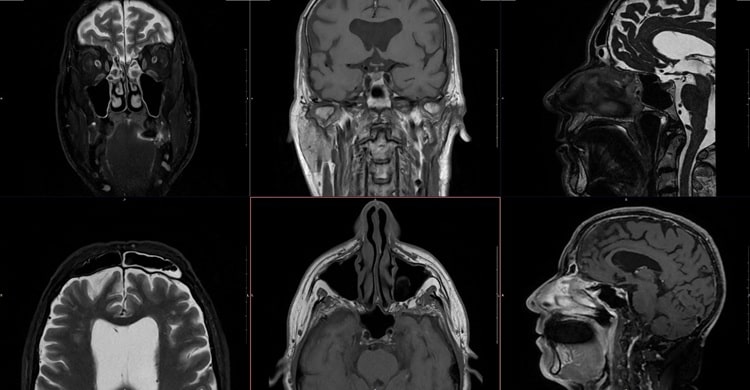

Ressonância magnética da face: exame preciso para detectar tumores na faringe e glândulas salivares

A ressonância magnética da face é um exame de imagem de alta resolução, utilizado para avaliar estruturas complexas da região facial.